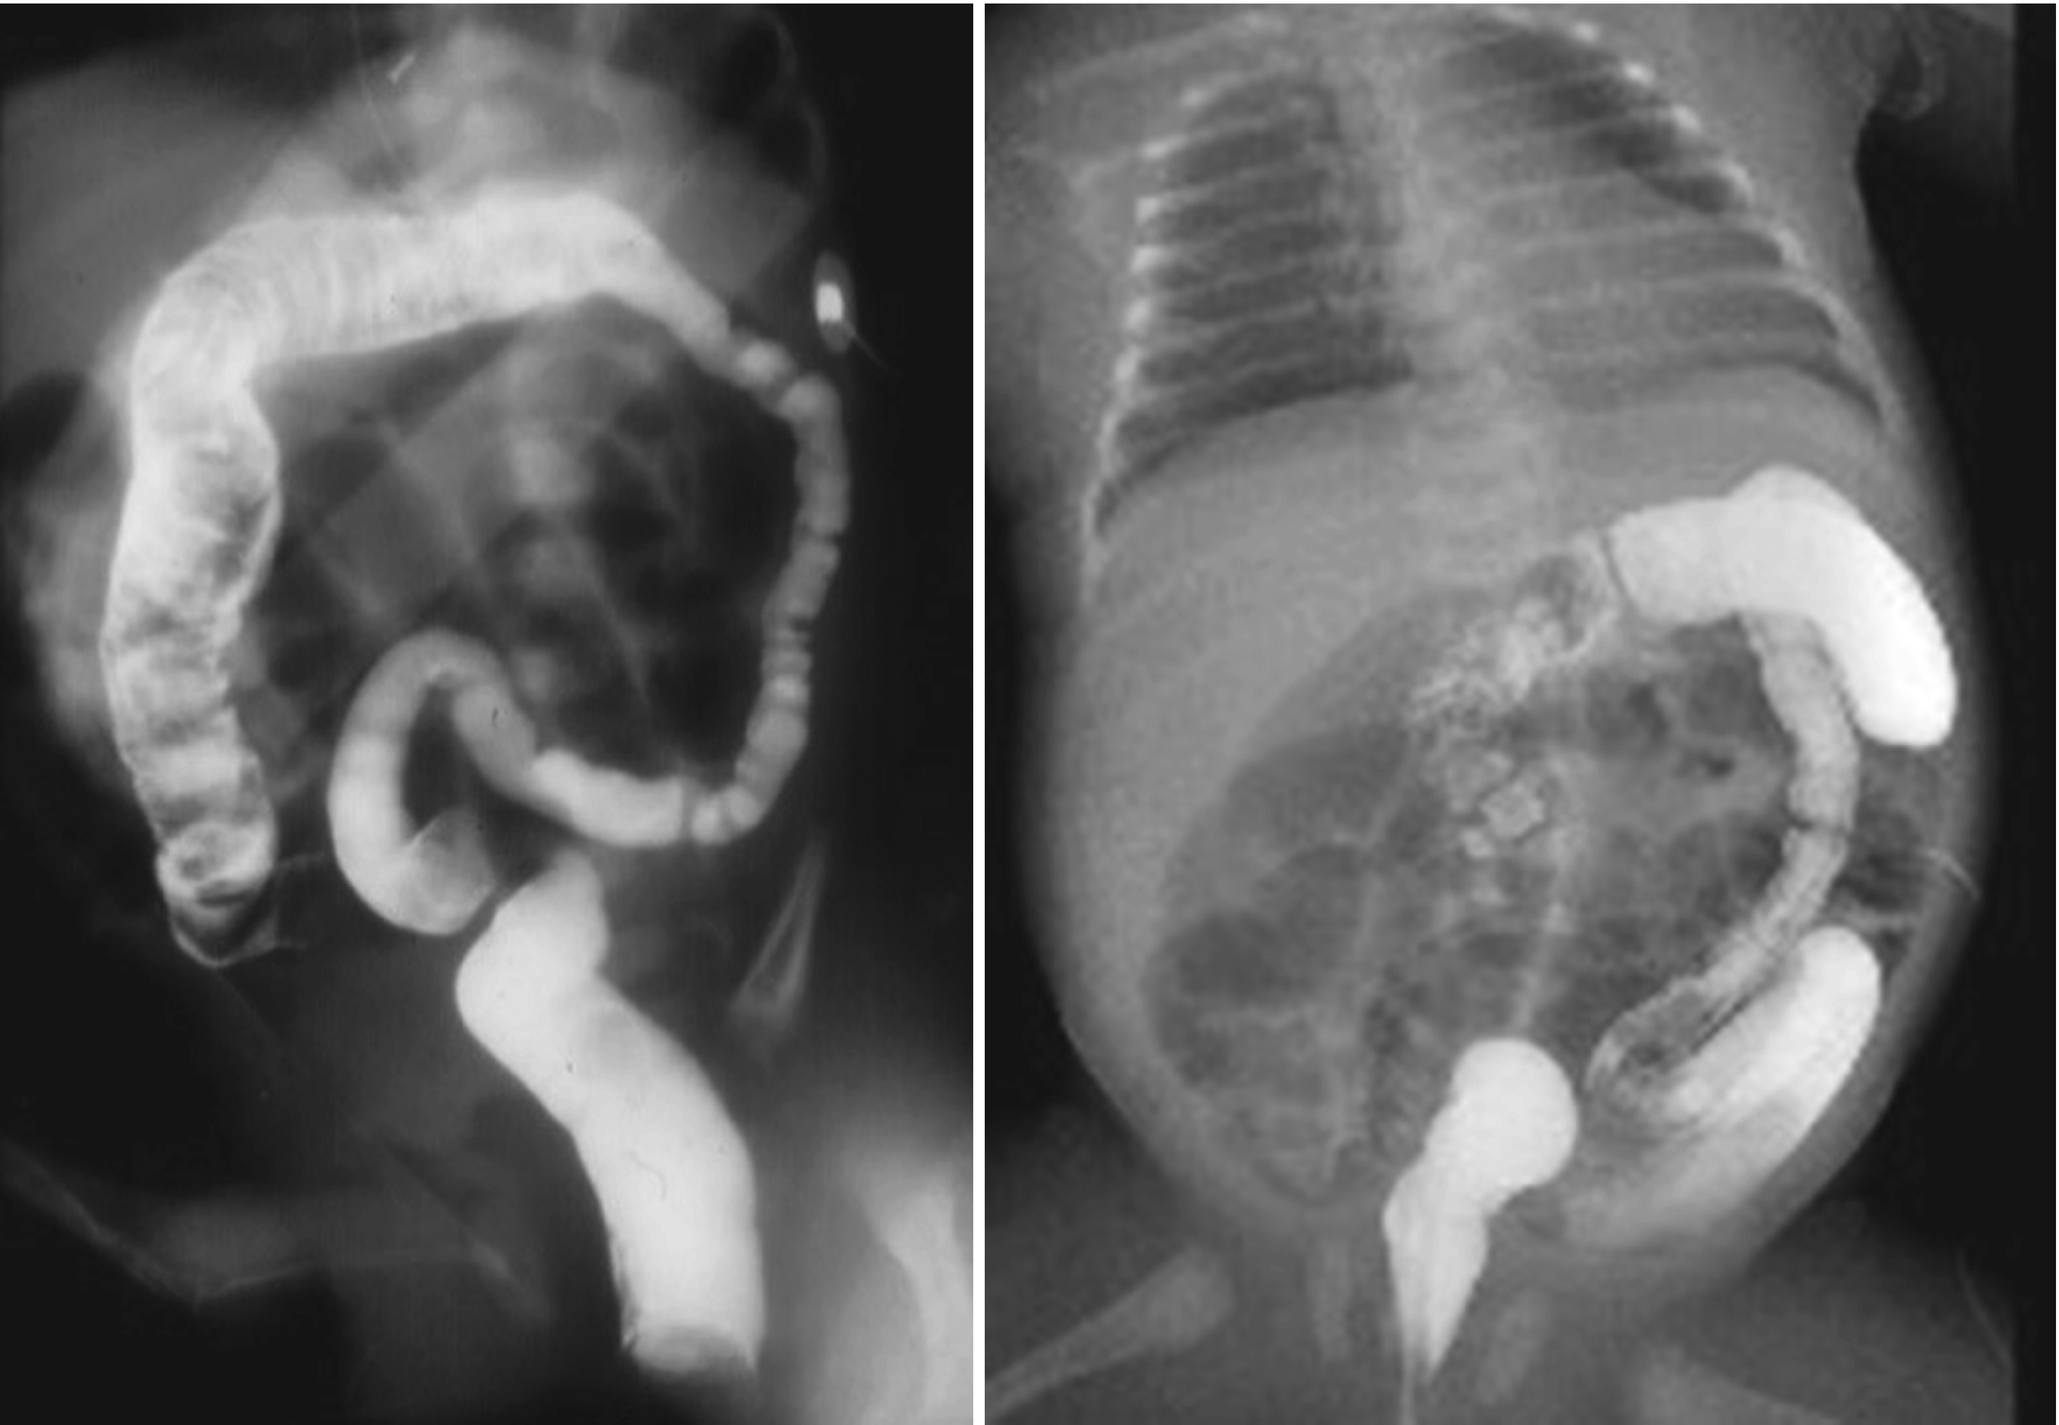

Occurrence in asymptomatic infants of diabetic mothers. Its etiology remains unknown but a significant association has been noted between maternal diabetes and small left colon. The diagnosis and treatment are assured by a simple contrast enema.

Small left colon sydrome is subset of meconium plug syndrome in which an enema demonstrates an apparent transition zone between the dilated and the normal-to. Plain abdominal radiographs show dilated intestinal loops. Affected patients have abdominal distention difficulty in initiating evacuation and sometimes vomiting.

An unusually high incidence 40 of maternal diabetes was observed in a series of 20 newborn infants who had low colonic obstruction and barium enema findings of a uniformly narrowed colon from the splenic flexure to the anus. Hyperglucagonemiawhich may result from hypoglycemiaor sepsis also leads to decreasedperistalsis in the left colonDecreased motility results in increasedabsorption of water from thecolon which eventuates in the formationof abnormal meconiumInfants with small left colon syndromepresent with progressive abdominaldistention vomiting and failureto pass meconium. Davis WS Campbell JB.

Meconium plug syndrome refers to a functional colonic obstruction in a newborn due to an obstructing meconium plug. Infants with small left colon syndrome present with progressive abdominal distention vomiting and failure to pass meconium. It is usually transient and affects the left colon with meconium plugging the bowel distal to this segment.